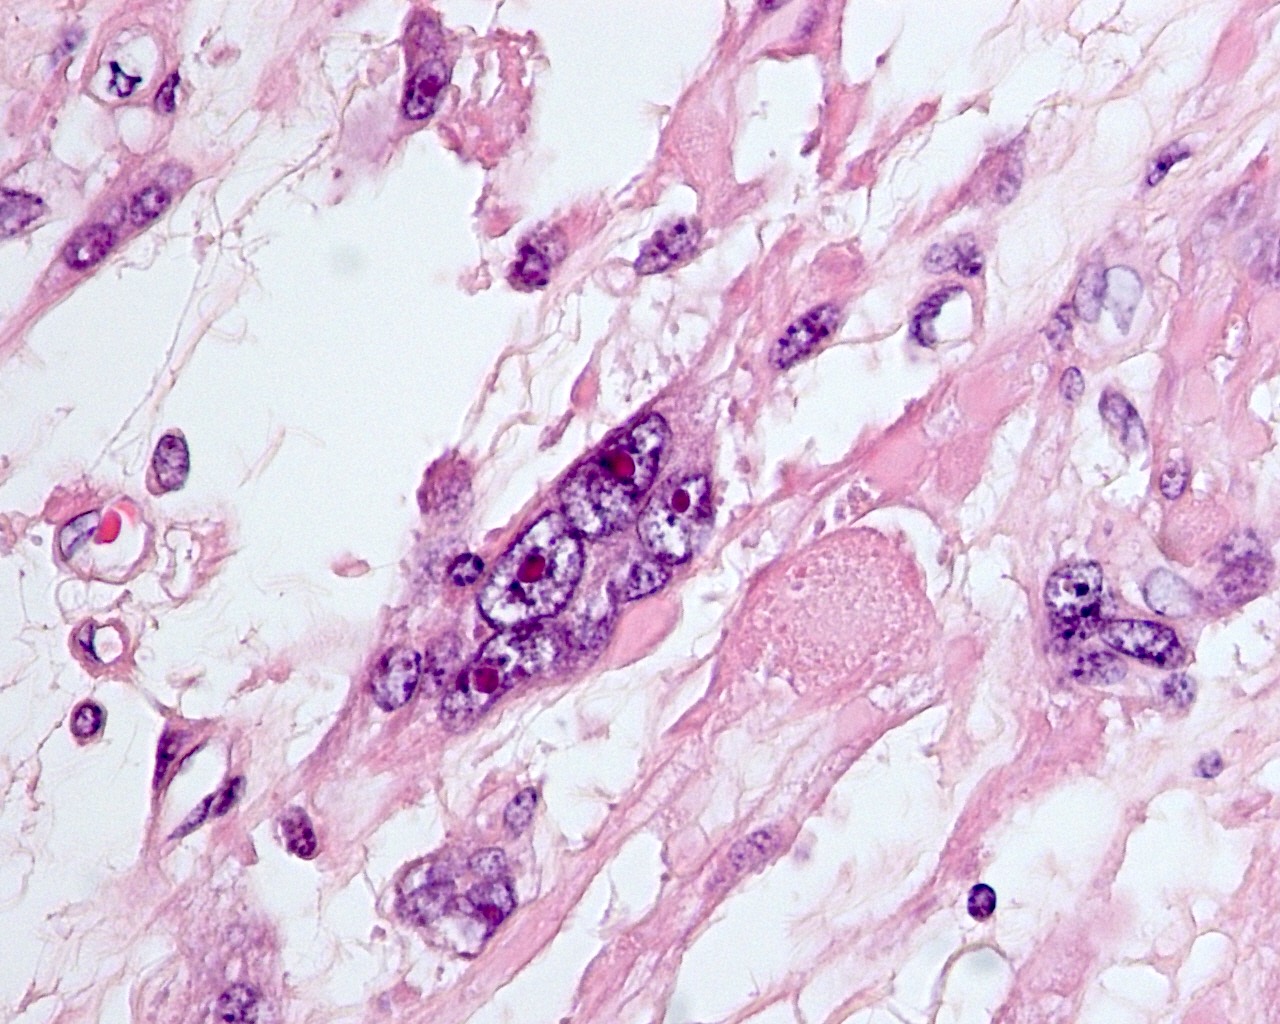

Microscopic (histologic) description

- Conventional / usual leiomyoma (spindle):

- Well defined borders

- Normocellular

- Intersecting fascicles of monotonous spindle cells with indistinct borders, eosinophilic cytoplasm, cigar shaped nuclei (with tapered ends) and small nucleoli

- Atypia: absent or mild

- Mitoses: rare (in general < 5/10 high power fields)

- Blood vessels with thick walls

- With or without infarct type necrosis, hyalinization, calcification, cystic change

- Leiomyoma with bizarre nuclei:

- Bizarrely shaped, hyperchromatic, multilobulated nuclei with nuclear pseudoinclusions

- Arranged in a multifocal to diffuse distribution in a background of a typical leiomyoma (Am J Surg Pathol 2014;38:1330, Mod Pathol 2017;30:1476, Am J Surg Pathol 2016;40:923, Cancer 2014;120:3165, Am J Surg Pathol 1997;21:1261)

- Alveolar edema, staghorn vessels

- Low mitotic activity (< 5 mitoses/10 high power fields)

- Absence of tumor cell necrosis

- Vasculature variable (staghorn vessels, thick walled vessels, fibrinoid necrosis of vessel walls, luminal vascular obliteration)

- Diagnostic key: intermixed normal spindled smooth muscle cells

Microscopic (histologic) images

Contributed by Sabrina Croce, M.D., Ph.D., Kristina Doytcheva, M.D., Jennifer A. Bennett, M.D. (Case #508) and @Andrew_Fltv on Twitter